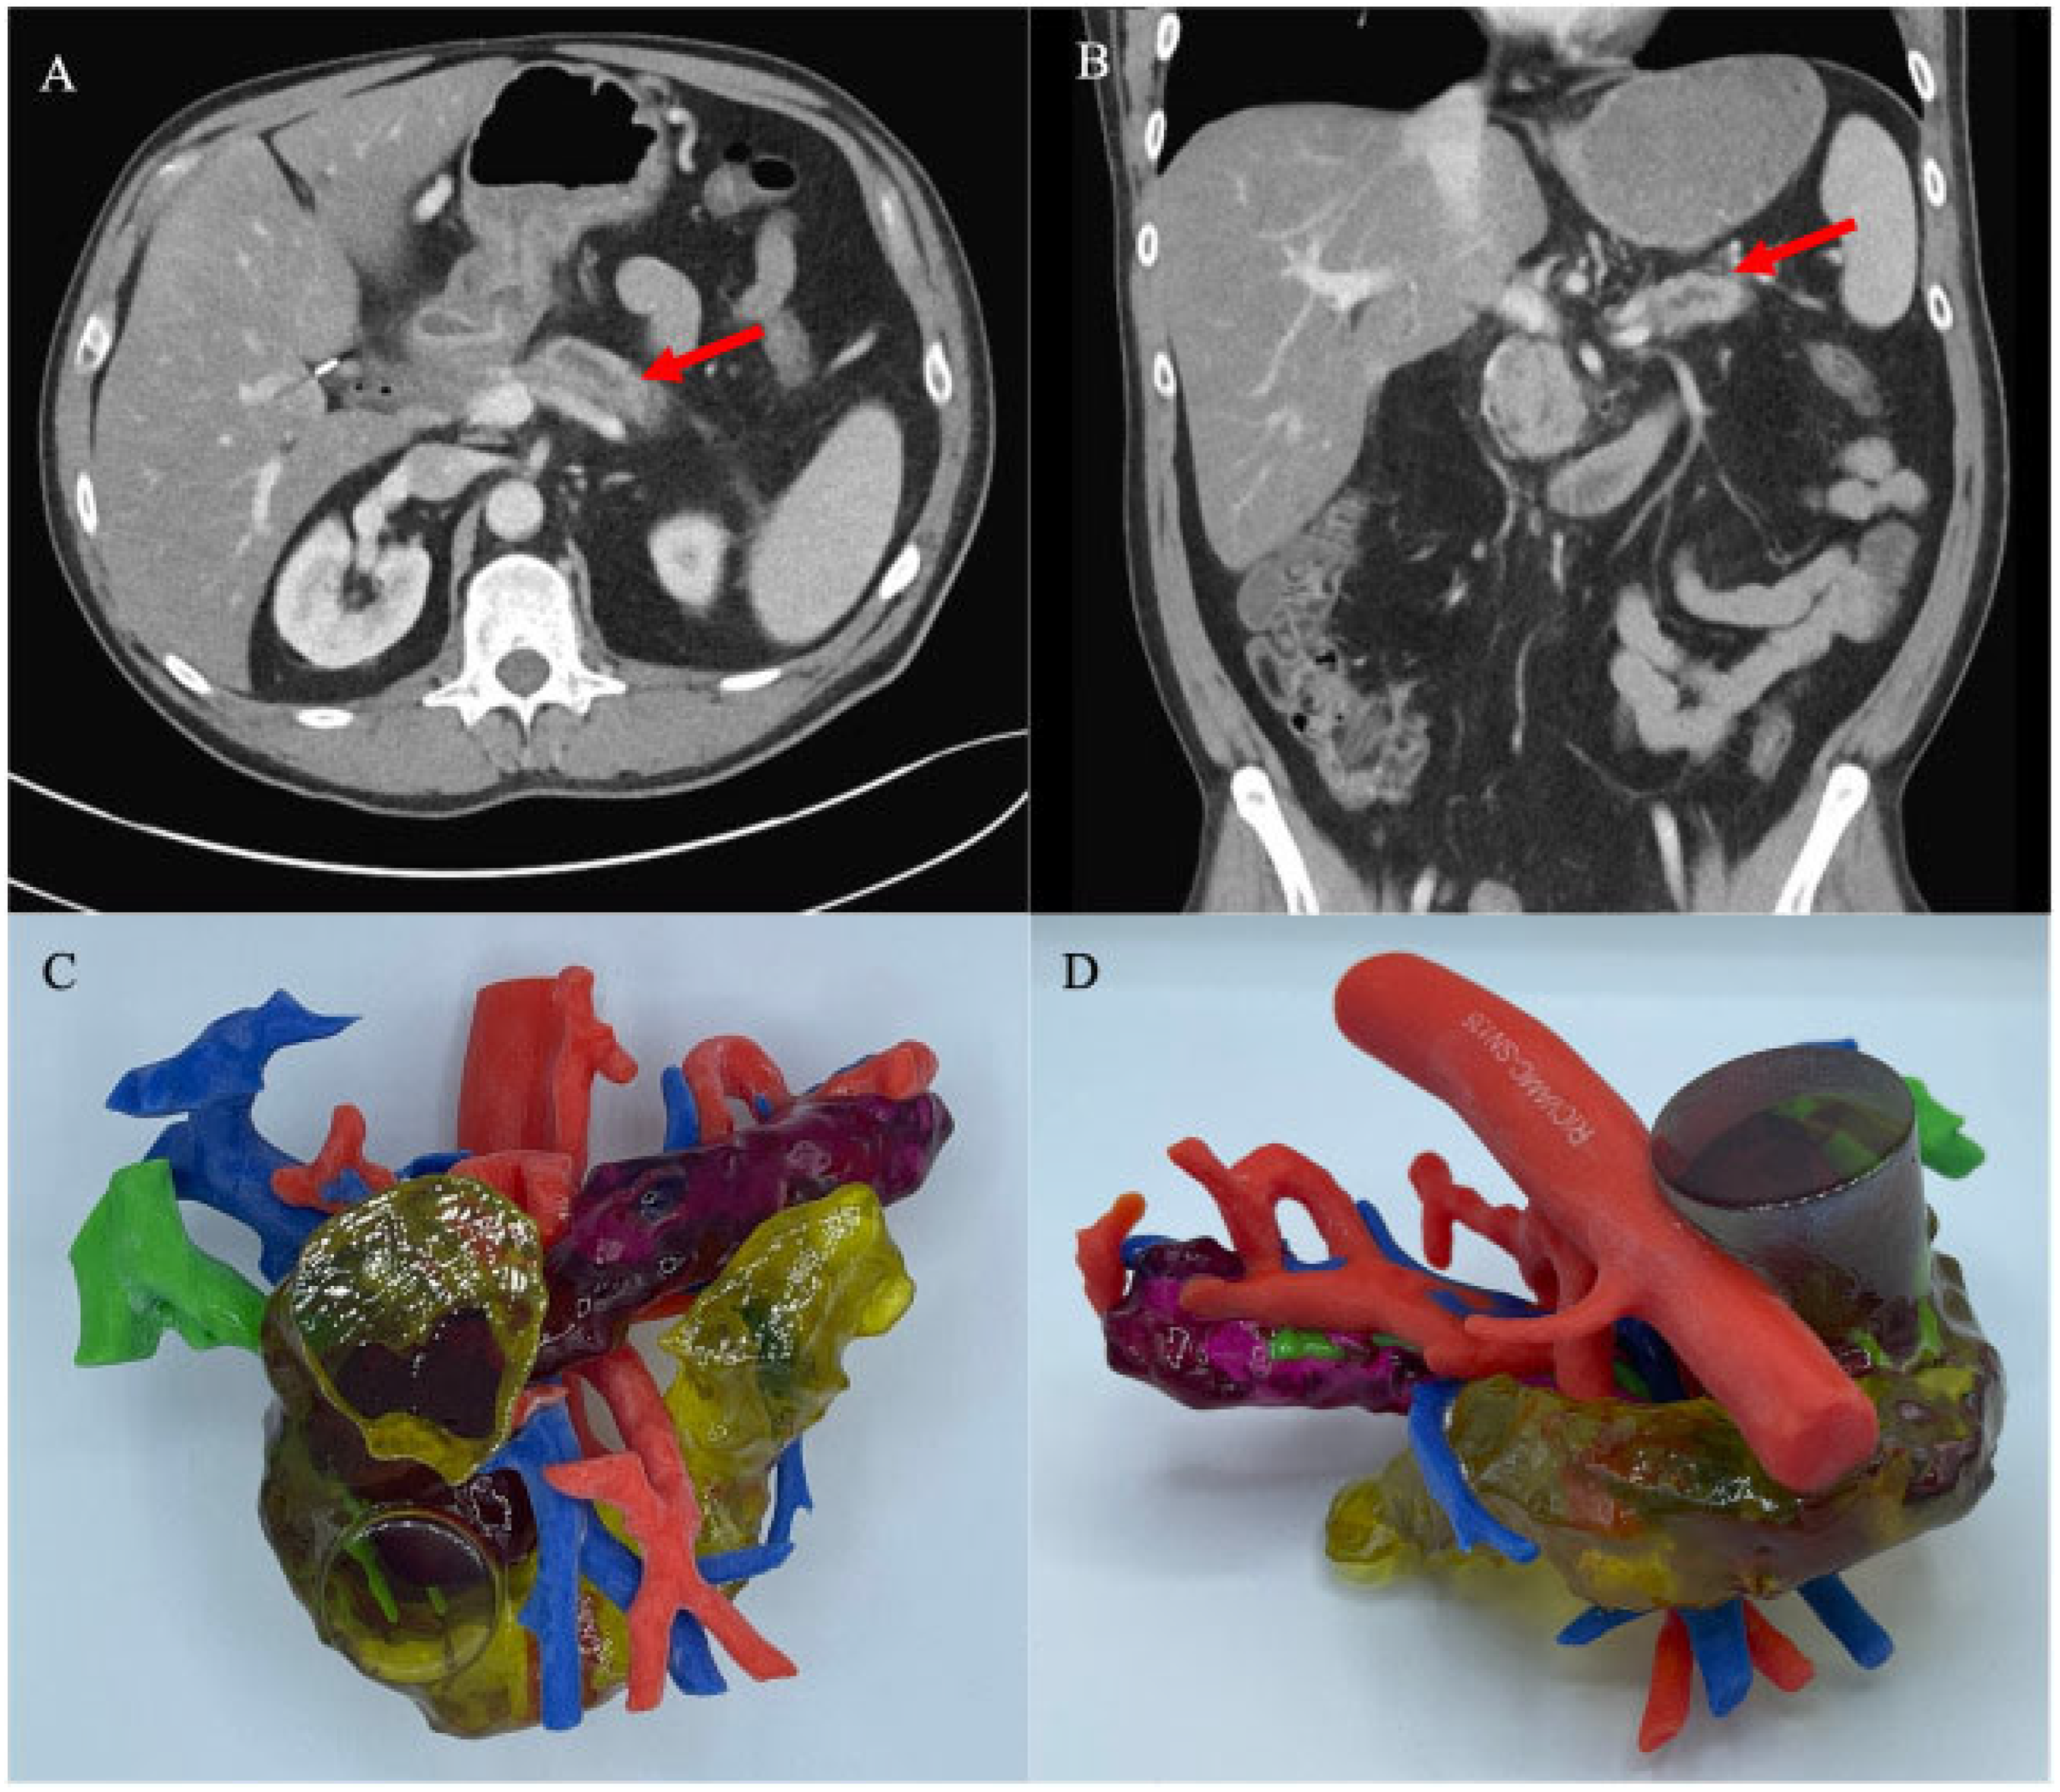

However, over the last decade, studies of 3D-printed gastrointestinal models have used only small sample studies or presented case reports (Figure 1). A review by Papazarkadas et al. highlighted the value of 3D printing in colorectal surgery [15]. However, the 3D-printed models in this review were only vascular, pelvic, and anorectal fistulas. There is a lack of systematic research on 3D-printed gastrointestinal tract models for surgical planning and medical training.

Figure 1. Three-dimensional-printed model of a case with a pancreaticogastric fistula. Axial and coronal (A,B) views of a CT abdomen/pelvis showing dilated pancreatic duct (red arrows). Initial 3D-printed model based on the above CT, color-coded as follows: red—aorta and arterial system, blue—portal venous system, green—biliary tree, yellow—duodenum, purple—pancreas; (C,D) show anterior and posterior views. Reprinted with permission under open access from Habermann et al. [13].